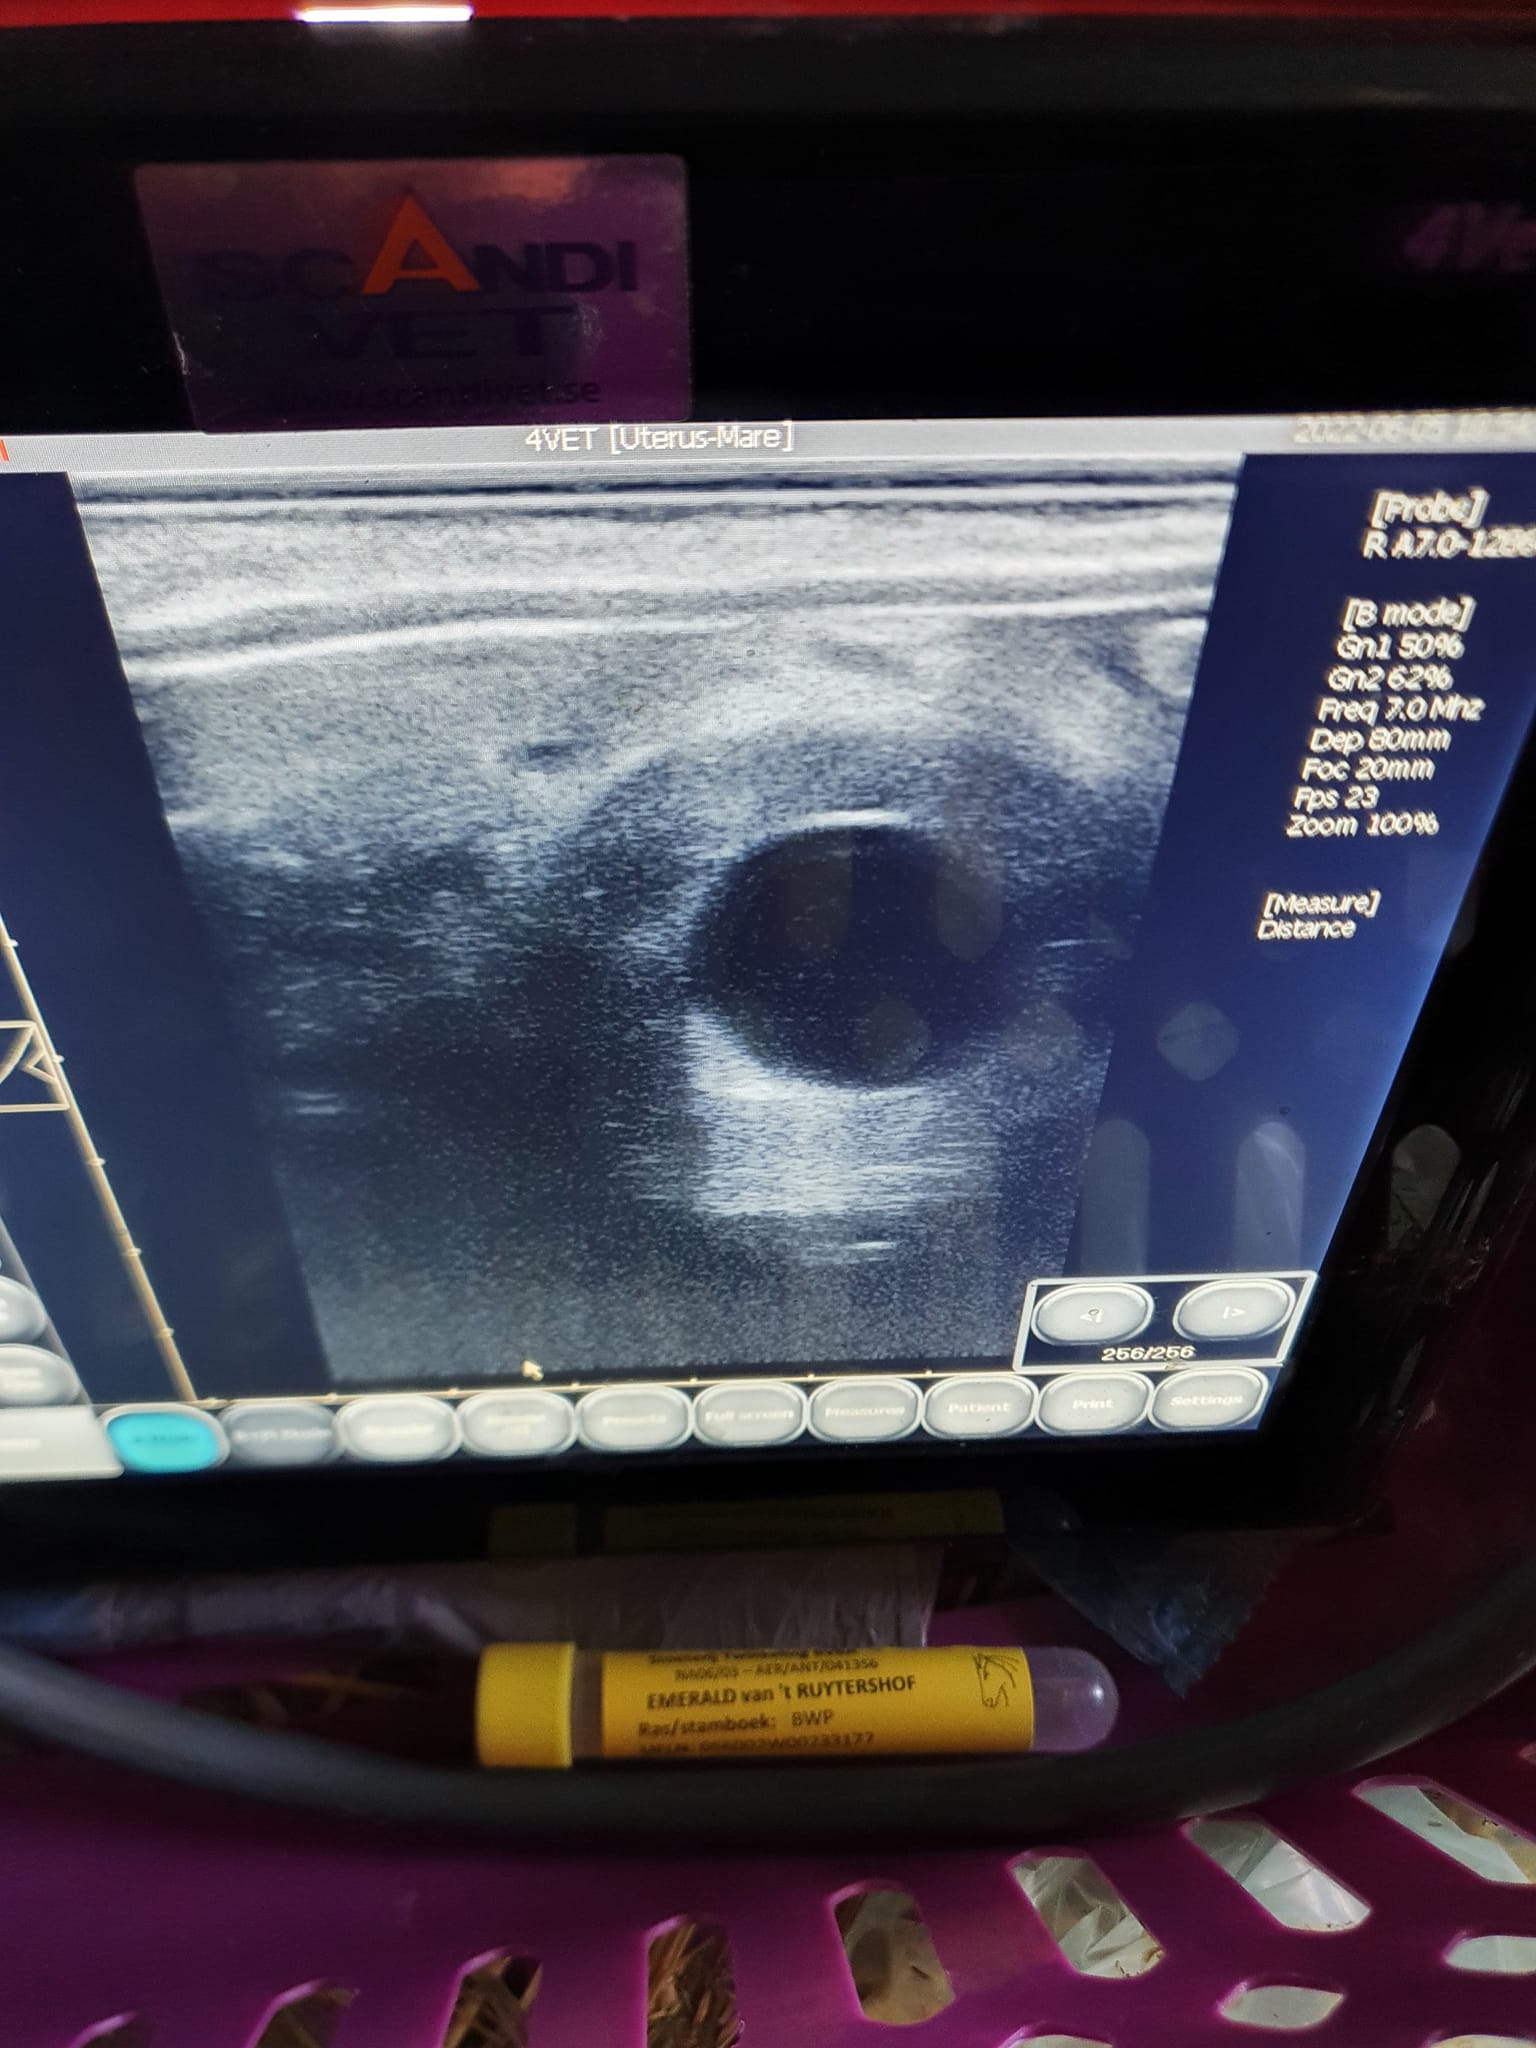

Semin, gynekologi, dräktighetsundersökningar

Seminverksamhet (TAI) sker i samarbete med Ingela Hansson på Ströamo semin sedan snart 20 år tillbaka. Här är lugnt och tryggt för sto och föl och vi har mycket goda dräktighetsresultat år efter år. Jag gör också dräktighetskontroller och gynundersökningar/åtgärder hemma i ditt stall.